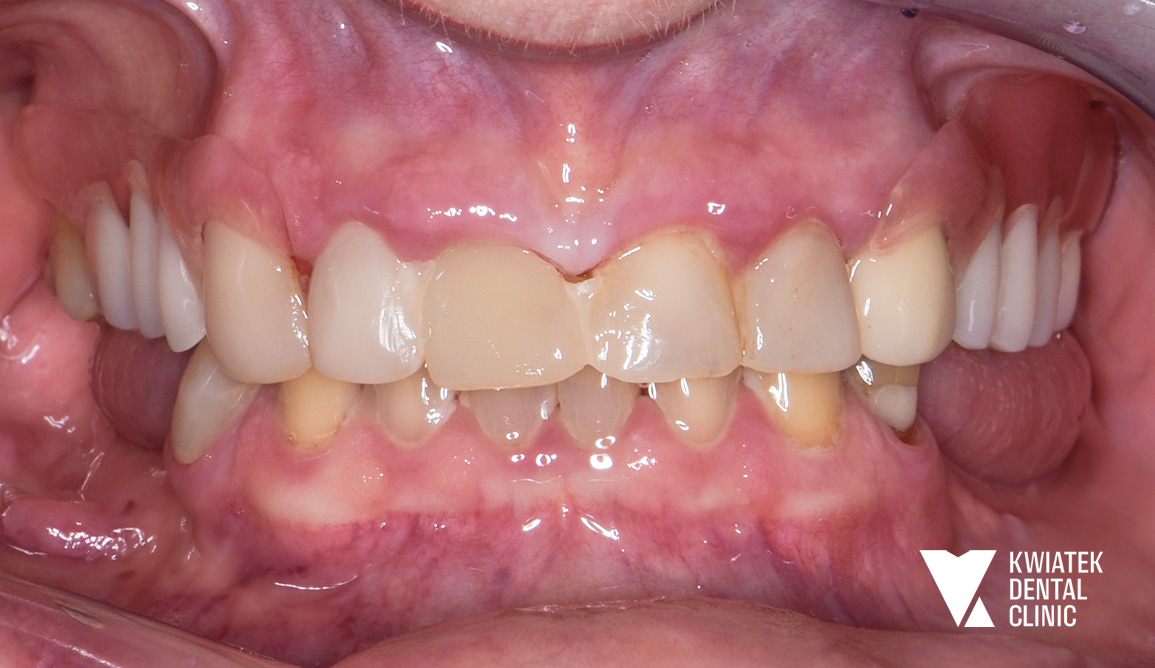

Pełna rekonstrukcja zwarcia i estetyki - historia wymagającej metamorfozy

Pacjent zgłosił się do kliniki z zaawansowanymi problemami stomatologicznymi: licznymi ubytkami próchnicowymi, brakami zębowymi, starciem zębów oraz zaburzeniami zwarcia. Leczenie obejmowało kompleksową diagnostykę, leczenie zachowawcze i endodontyczne, zabiegi chirurgiczne, implantację oraz wieloetapową odbudowę protetyczną. Efektem terapii jest perfekcyjnie zbalansowany zgryz, najwyższy komfort funkcjonowania oraz naturalnie piękny uśmiech, który podkreśla indywidualny charakter pacjenta i pozwala mu w pełni cieszyć się nim każdego dnia.